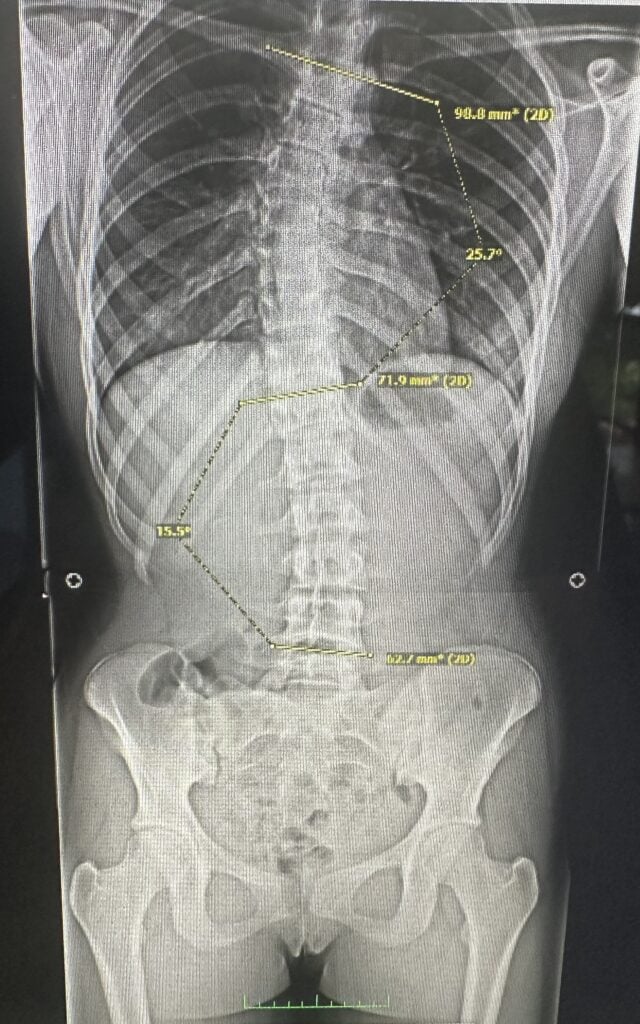

Scoliosis is a complex condition, and the spine itself should be evaluated and treated by a scoliosis-trained healthcare professional (Shroth Physical Therapists are the BEST!) who can provide individualized care. While curves can be categorized into specific curve types, your curve is truly unique to you based on (but not limited to) the apex, Cobb angle, amount of axial rotation and torsion, type of scoliosis, and other health, structural and environmental factors.